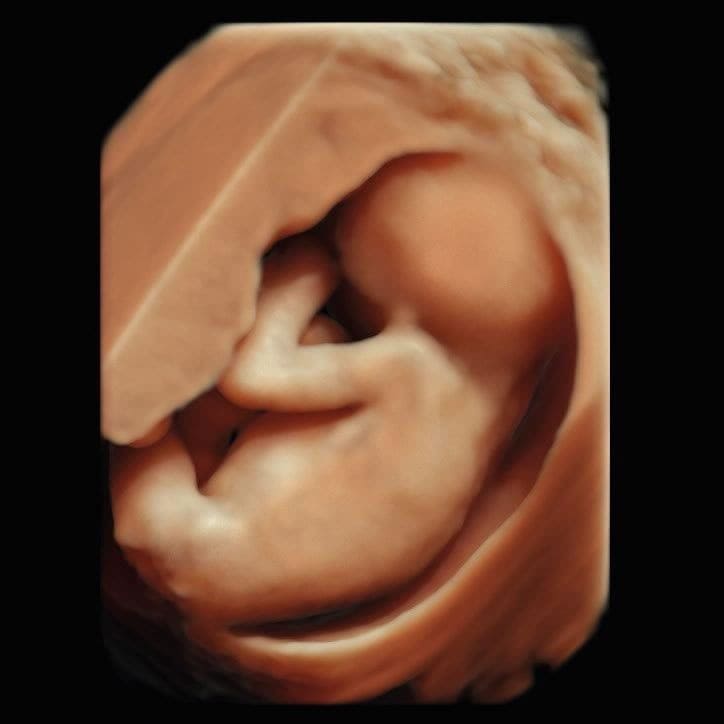

Im ersten Trimenon (1. Schwangerschaftsdrittel) bieten wir Ihnen verschiedene Untersuchungen an. Ab der 12. SSW können unter anderem bereits Kopf, Herz und Extremitäten untersucht und einige Fehlbildungen ausgeschlossen werden.

Im Ersttrimesterscreening (12-14 SSW) können wir durch Messen der Nackentransparenz, Darstellung des Nasenbeins und weitere Parameter zusätzlich das Risiko für Chromosomenstörungen bei Ihrem Kind ermitteln.

Ultraschall Ersttrimester Screening